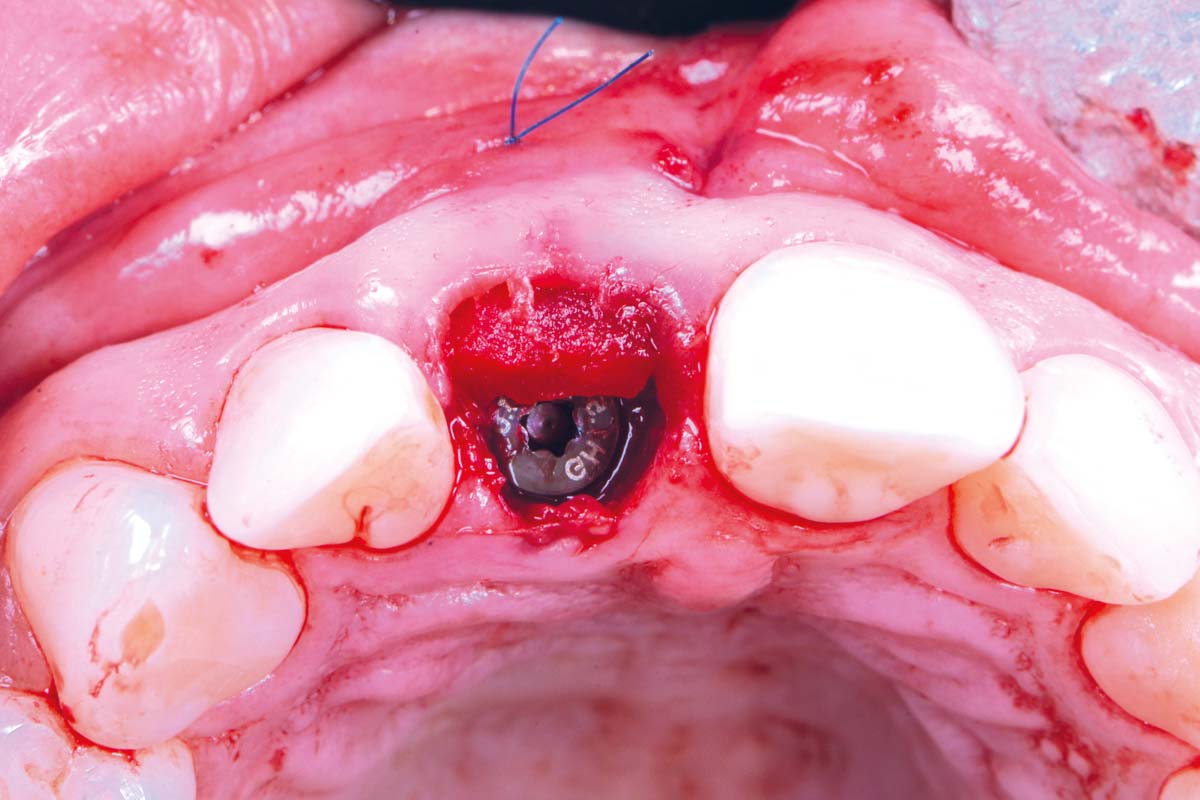

11/30 - Bone profiler was used to remove supracrestal boneExcellent aesthetic result of buccal augmentation with mucoderm® and maxgraft® after immediate implant placement - 3-years follow-up - Dr. A. Puišys